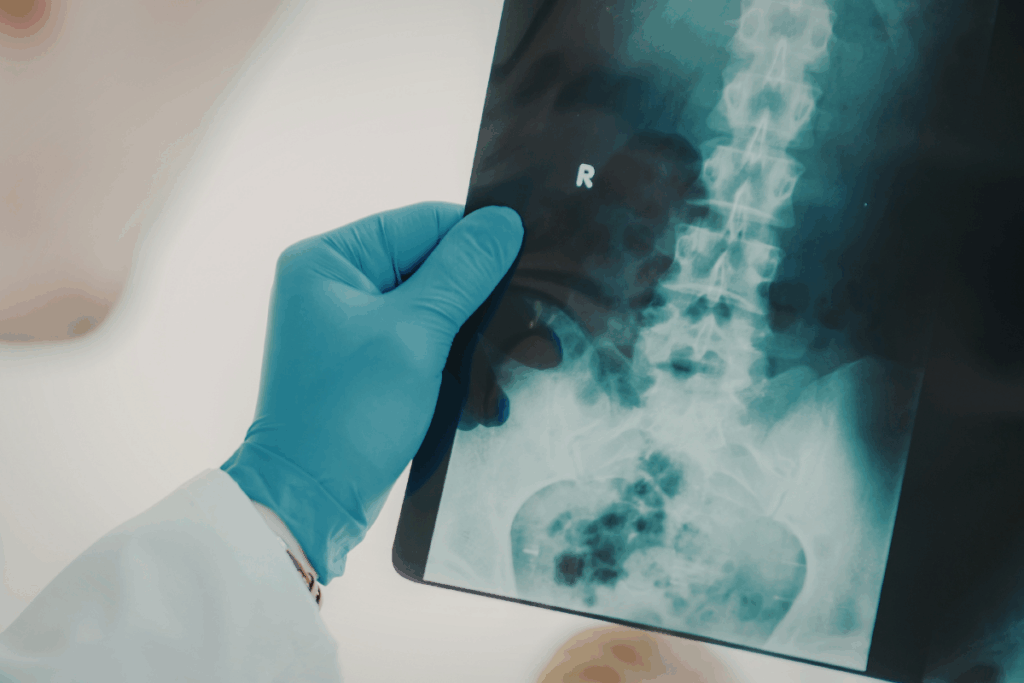

Radiological and histological examinations showed that there was severe vertebral bone damage. Micro-computed tomography revealed a large number of structural lesions in the vertebrae, especially around the lumbar and thoracic regions of the spine. There were vertebrae with little holes, as well as those with general structural disintegration. Additional tissue examination showed significant bone loss within the vertebral bodies. Marrow adiposity and degeneration of intervertebral discs were also observed in the damaged bones. Although these bones had abnormalities, the other major organs, like the liver, heart, kidney, and pituitary, were normal, implying that the abnormality was more localized in the maintenance processes of bones. The researchers studied embryonic tissues in order to identify the time when the problem developed. Although CL-11 and complement protein expression were common in embryonic bone formation, the embryos that were free of CL-11 and C3 were found to be normal skeletally at birth. This suggests that the defects are later on because of issues with bone remodeling as opposed to early development.